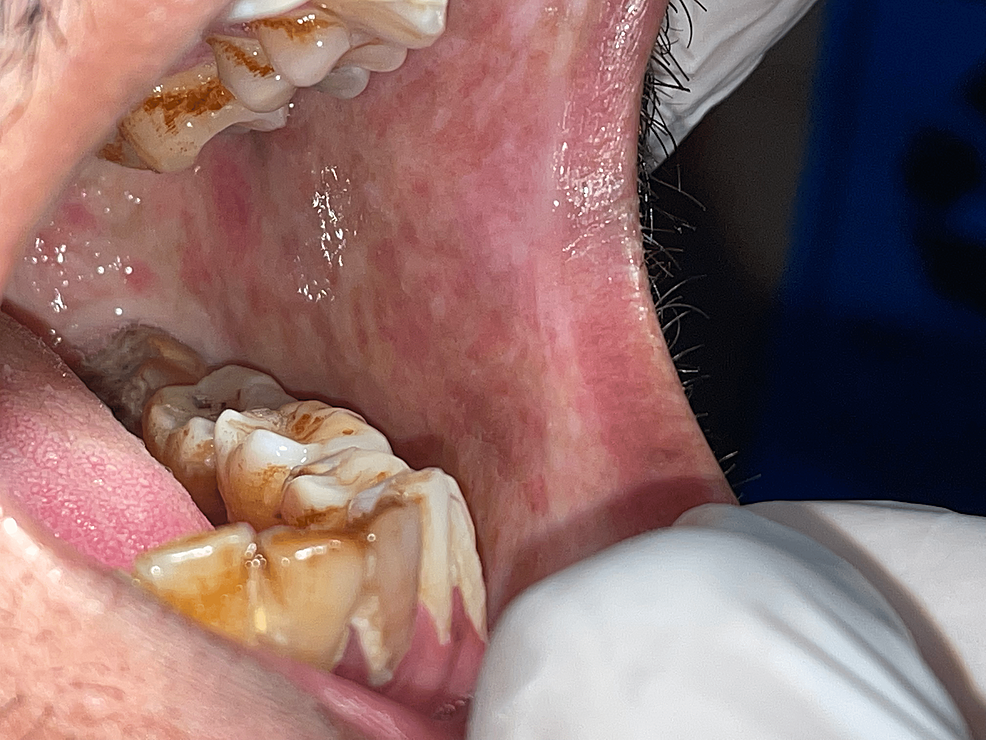

Tobacco Pouch Keratosis Biopsy . this paper presents features of tobacco pouch keratosis and aims to highlight the oral effects of smokeless tobacco, management, and. The characteristic appearance is a gray/white mucosal discoloration with a wrinkled or fissured surface texture. the histologic features of frictional keratosis from the tongue, lip or buccal mucosa vary slightly depending on. there is a strong association between tobacco use and the development of mucosal white patches such as tobacco. Smokeless tobacco keratosis is a reversible alteration of the oral mucosa in immediate contact with a smokeless tobacco product (chewing tobacco, moist snuff, dry snuff). smokeless tobacco keratosis presents as a characteristic white corrugated plaque on the oral mucosa where the tobacco is placed.

there is a strong association between tobacco use and the development of mucosal white patches such as tobacco. The characteristic appearance is a gray/white mucosal discoloration with a wrinkled or fissured surface texture. this paper presents features of tobacco pouch keratosis and aims to highlight the oral effects of smokeless tobacco, management, and. smokeless tobacco keratosis presents as a characteristic white corrugated plaque on the oral mucosa where the tobacco is placed. the histologic features of frictional keratosis from the tongue, lip or buccal mucosa vary slightly depending on. Smokeless tobacco keratosis is a reversible alteration of the oral mucosa in immediate contact with a smokeless tobacco product (chewing tobacco, moist snuff, dry snuff).